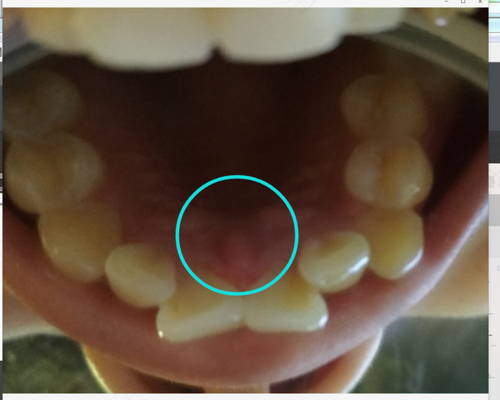

牙龈肿痛是现在生活节奏太快的人群经常会有的一种病,特别是在天气干燥炎热的夏天,那么,如果牙龈肿痛该怎么办?吃些什么可以慢慢恢复?这两个问题想必很多人都会想注意的,接下来介绍一下。

牙龈肿痛怎么办